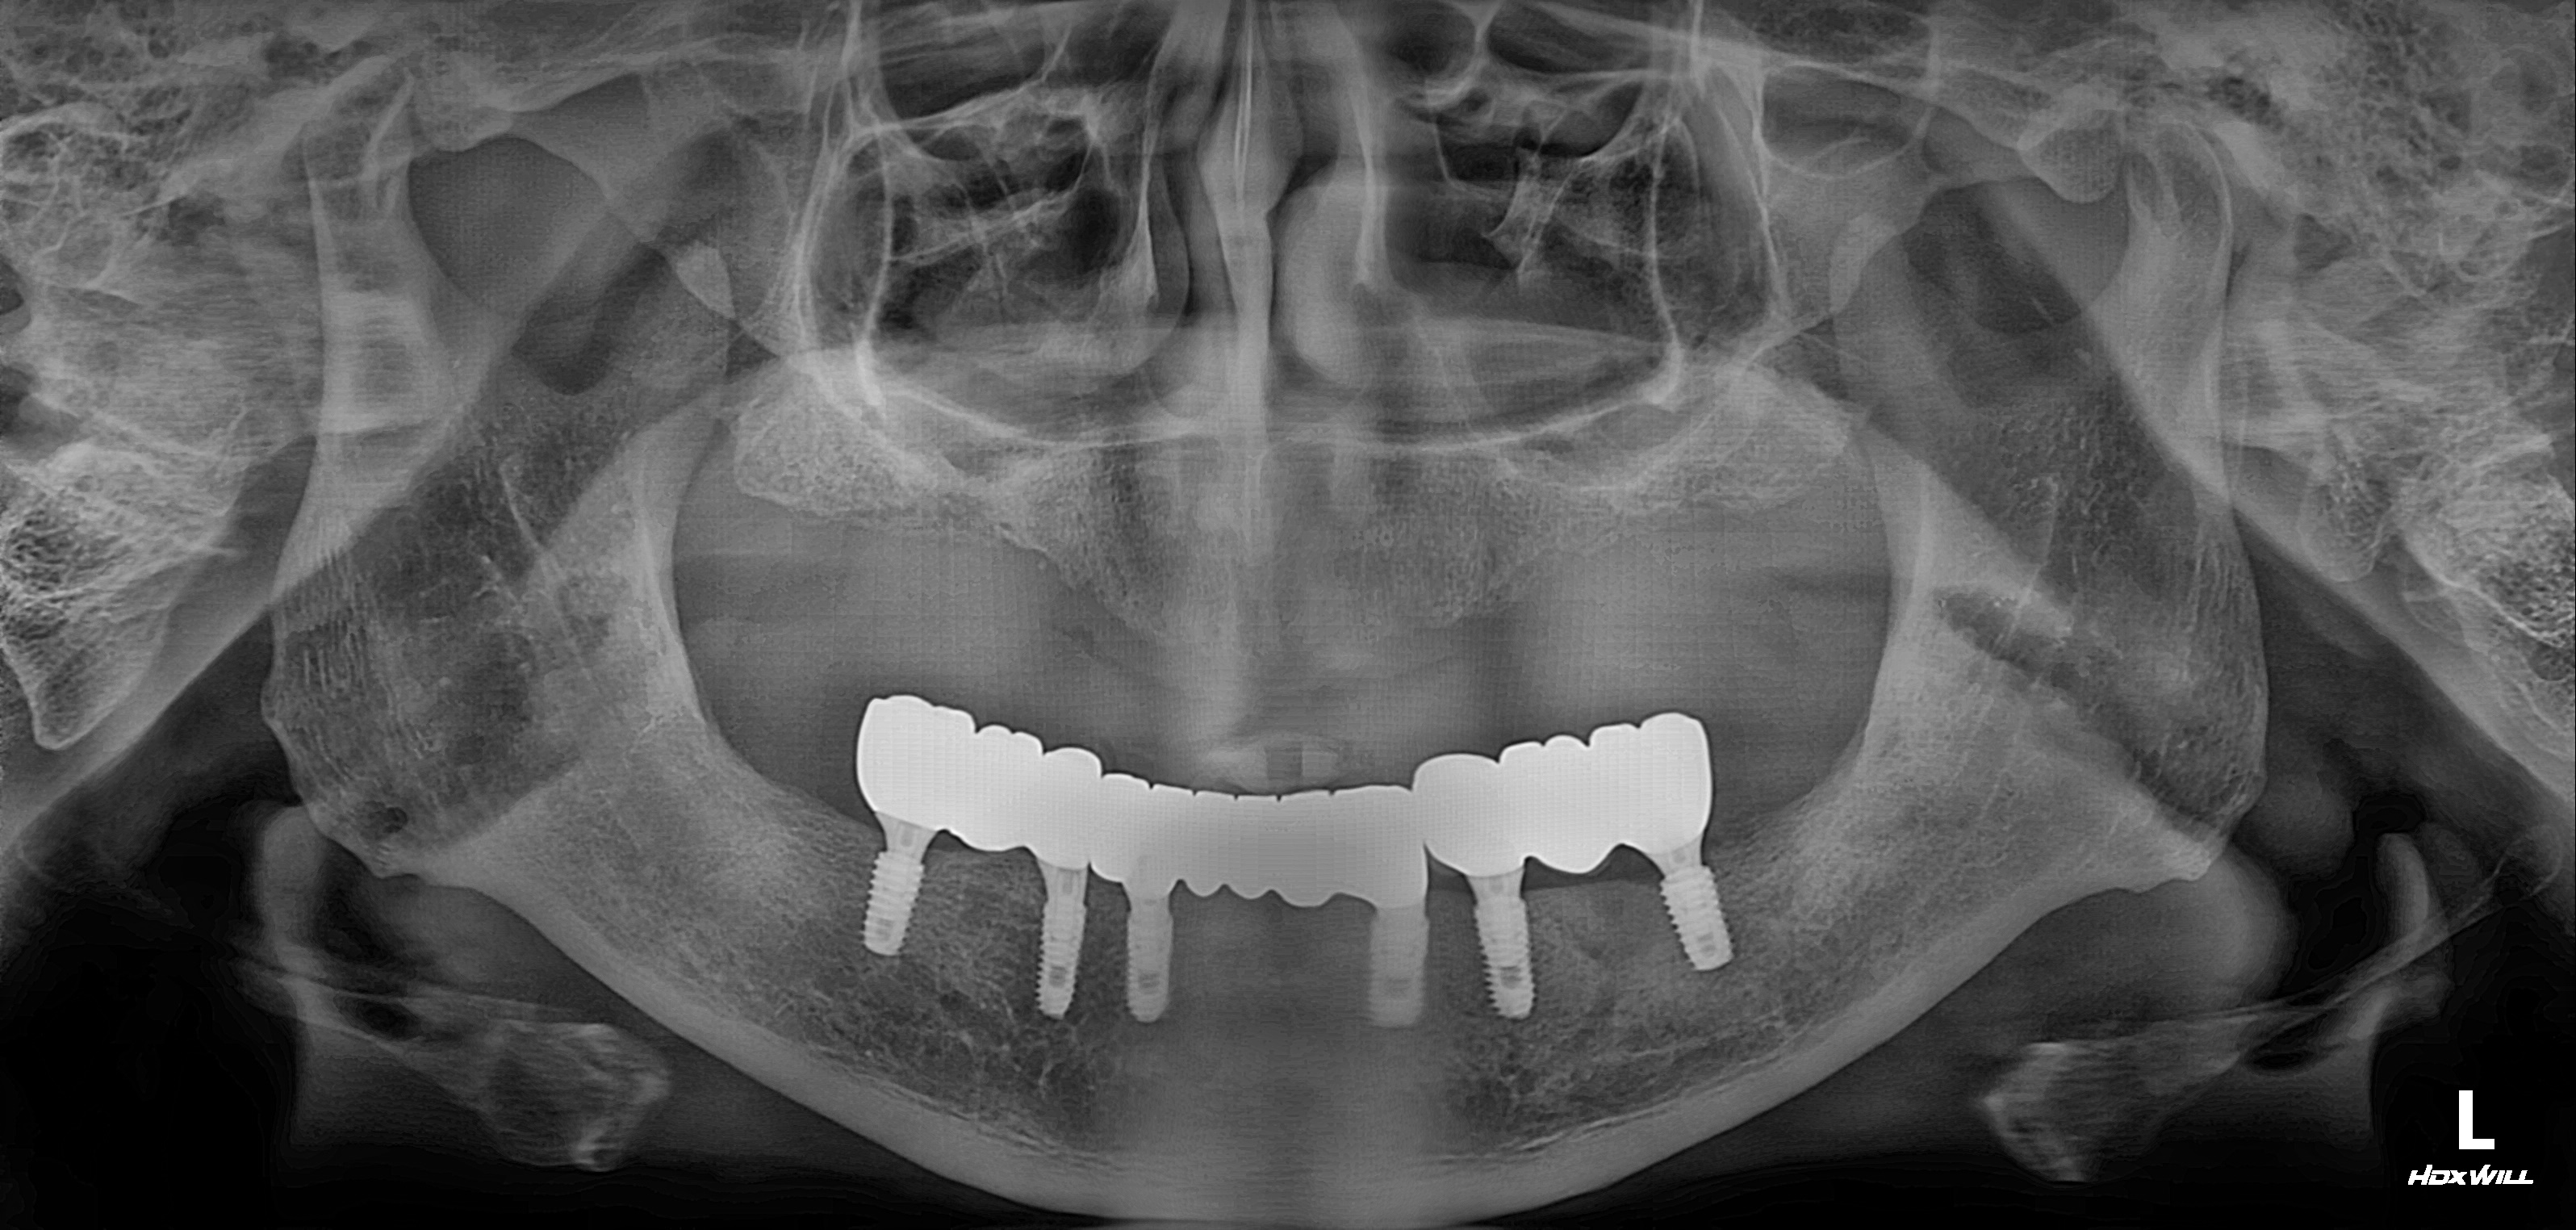

전악임플란트 식립사례

전후사진

전악 임플란트 식립사례